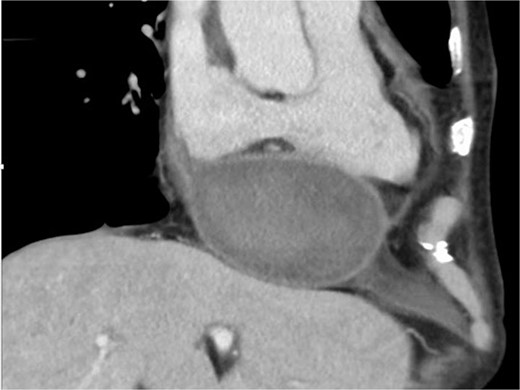

Two months later, follow-up computed tomography revealed a huge pseudoaneurysm (110 × 57 mm) on the posterior side of the LV (Fig. 2). Based on TTE confirmation of blood flow into the pseudoaneurysm, a second operation was performed because of the high risk of cardiac rupture.

Computed tomography scan at 2 months after left ventricular rupture repair. There is a huge pseudoaneurysm (110 × 57 mm) on the posterior side of the left ventricle.